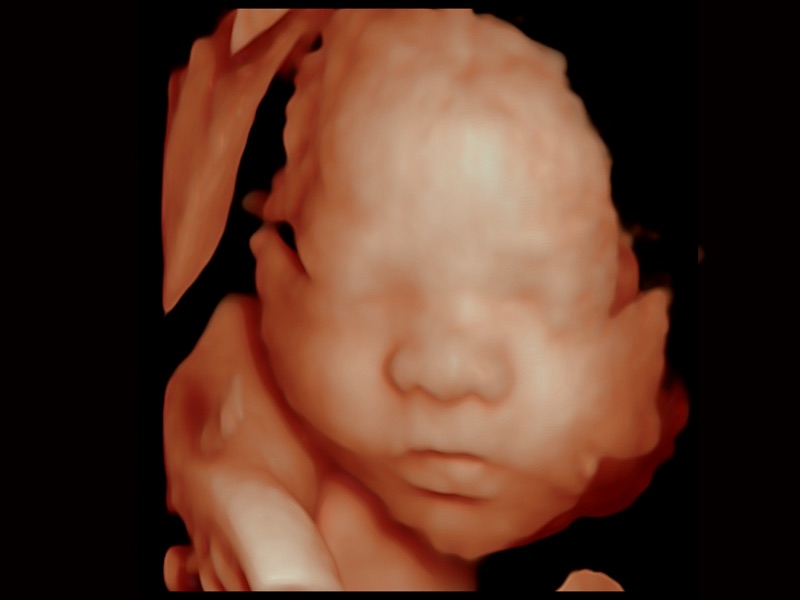

Renderizado de rostro fetal con S-Live

• S-Live Silhouette

A través de la aplicación de una fuente de luz virtual y un efecto de sombra, S-Live Silhouette ve a través de la superficie y delinea claramente los contornos de huesos, órganos, cavidades, paredes de los vasos y otras estructuras internas. Es una herramienta beneficiosa para identificar anatomía normal y diagnosticar malformaciones congénitas complejas.